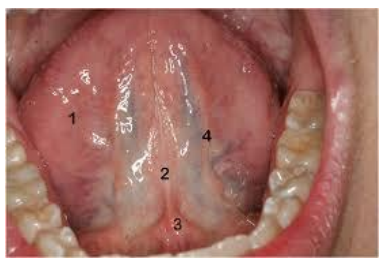

Observe a imagem abaixo:

Assinale a alternativa que apresenta o correto nome da estrutura de número 3: